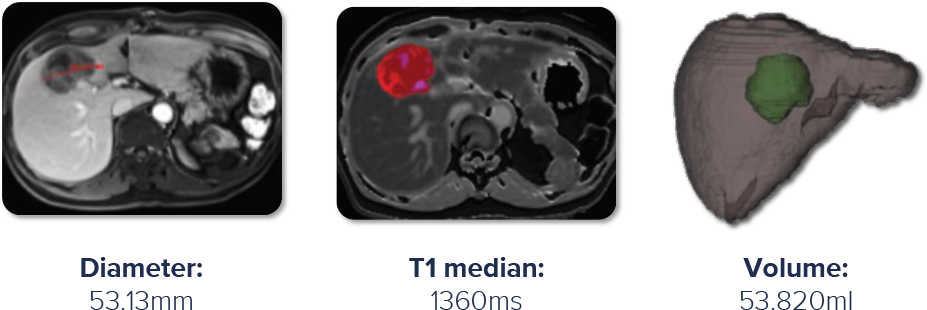

Revolutionizing oncology trials through expert central reads with improved standardization, reproducibility, quantitative organ health metrics, and tumour burden metrics. Allowing sponsors to characterize disease burden better and monitor tumor progression and response to treatment.

Enhanced screening and monitoring with cT1

cT1 better identifies patients for enrolment, more accurately detects early efficacy signals and pseudo-progression, and quantitatively monitors drug-induced liver injury.